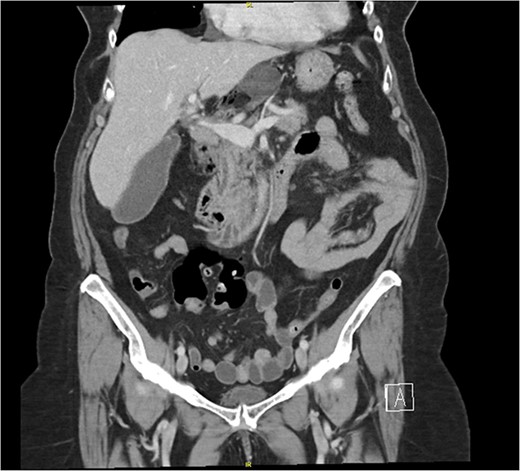

The patient’s laboratory values were significant for WBC 12.2 × 109/L, potassium 3.1 mmol/L, creatinine 0.59 mg/dl, lipase 676 U/L, total bilirubin 1.8 mg/dl, direct bilirubin of 0.6 mg/dL, ALT/AST 147/221 U/L, and alkaline phosphatase of 579 U/L. A computed tomography (CT) scan of the abdomen and pelvis with intravenous contrast demonstrated the cecum herniating through the foramen of Winslow with no signs of ischemia or bowel obstruction (Fig. 1); the gallbladder was distended with pericholecystic stranding and surrounding portal triad inflammation (Fig. 2).

A computed tomography (CT) scan of the abdomen and pelvis with intravenous contrast demonstrating a distended gallbladder with pericholecystic stranding and surrounding portal triad inflammation.